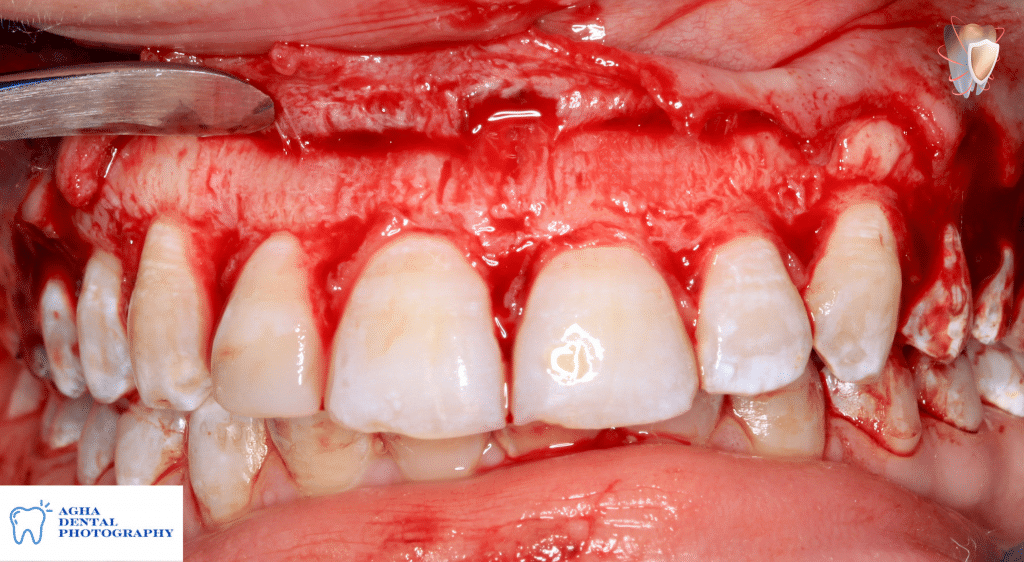

Elevation of a full thickness envelope flap revealing an irregular & thick labial bony

Rechecking biologic space confirming that it is insufficient "less than 2mm"

Ostectomy for correction of insufficient biologic space using rose head stone bur

Osteoplasty to reshape the labial plate of bone using a flame shaped stone bur

After finishing ostectomy & osteoplasty creating sufficient even biologic spaces of 2mm "from CEJ to crest of alveolar bone" & correcting thick bony ledges & irregular architecture of labial plate of bone

Flap suturing using 5/0 polyglycolic "vicryl" sutures with single sling suturing technique

After finishing flap suturing